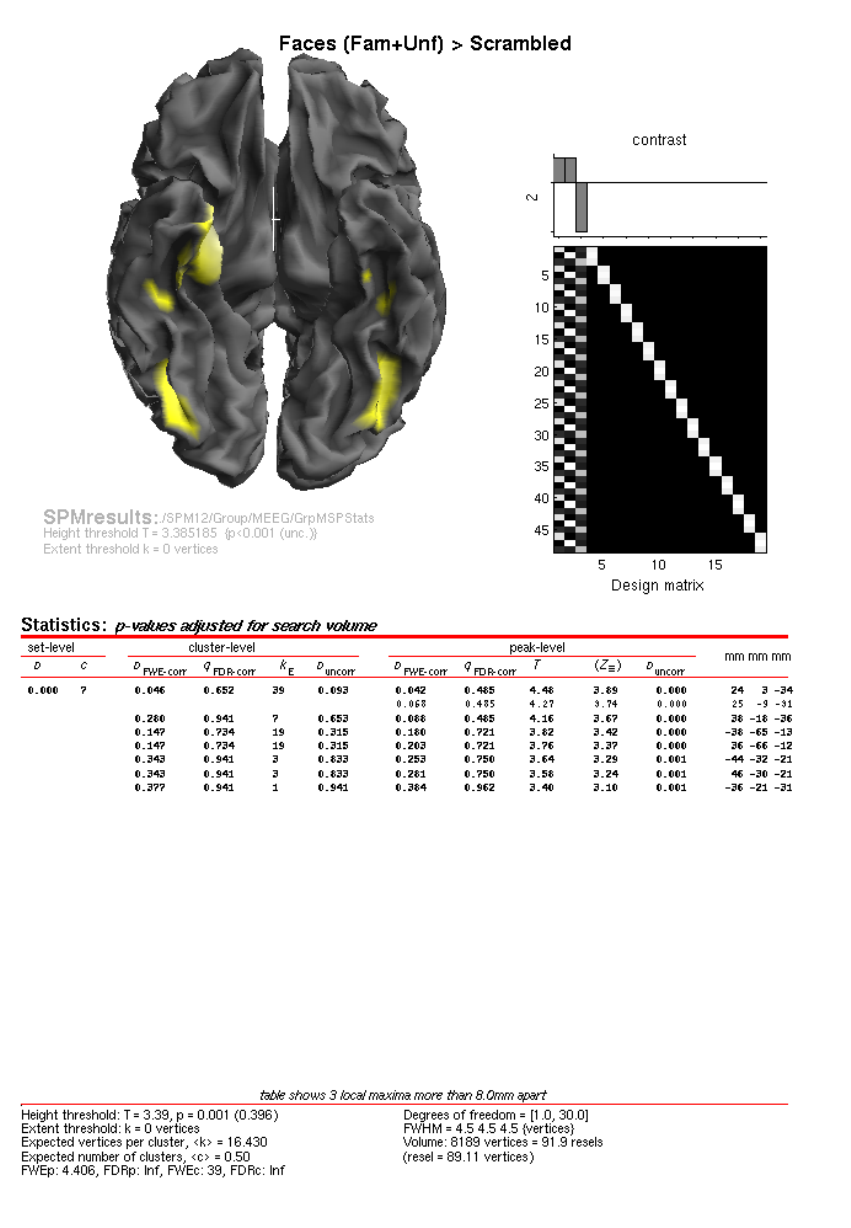

- Dynamic Causal Modelling for M/EEG

32 Face group fMRI data 271

32.1 Introduction ........................................271

32.2 Data ............................................271

32.3 Canonical HRF ......................................272

32.4 Informed basis set ....................................274

32.4.1 Nonsphericity ...................................276

32.4.2 Informed Results .................................276

32.4.3 T- and F-contrasts ................................280

32.5 FIR basis set .......................................282

32.5.1 Nonsphericity again ...............................283

32.5.2 FIR Results ....................................286

42.7.9 Group Statistics on fMRI data .........................425

42.8 Source Reconstruction ..................................425

42.8.1 Create Head Model ................................427

42.8.2 Model Inversion .................................428

42.8.3 Time-frequency contrasts ............................428

42.8.4 Group Statistics on Source Reconstructions ..................431

42.9 Group Source Reconstruction ..............................433

42.9.1 Group Statistics on Source Reconstructions ..................433

42.10Group MEEG Source Reconstruction with fMRI priors ................433

42.10.1 Group Statistics on Source Reconstructions ..................435